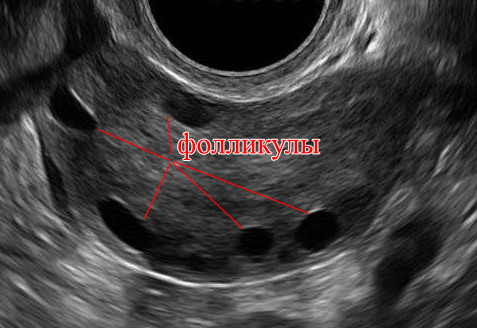

Но в картинке неточность. На самом деле яичник выглядит так:

Эти черные кружки - фолликулы. И за один менструальный цикл тратится не один фолликул. А десятки и сотни. Один фолликул, самый чувствительный - становится доминантным, остальные уменьшаются и исчезают. Образование новых фолликулов и исчезновение не доминантных - постоянный процесс. Не останавливающийся даже во время беременности.